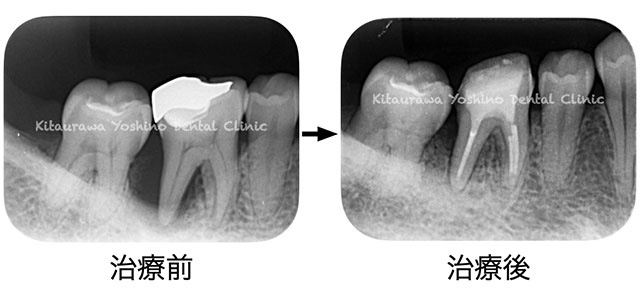

この調査は、1)一般歯科医、2)歯周病専門医(歯槽膿漏の治療専門医)、3)口腔外科専門医(顎の骨の再建やインプラントの治療専門医)、4)補綴専門医(入れ歯などの治療専門医)、5)歯内療法専門医(歯の内部の神経や根の治療専門医)を含む合計293名のそれぞれの異なる専門医に、同一患者の患歯(病気がある歯)を診てもらい、異なる専門医間でそれぞれ5つの異なる治療方針: “1)治療しない、2)歯を抜きインプラント、3)歯の治療、4)手術を含むその他の治療方法、5)患者さんとの相談の上決める”を決定してもらい、その治療選択の違いを専門医間で比較検討しました。

特に注目したいのは、今回の症例で歯を抜いてインプラント治療を行なう治療方法を選択した一般歯科医とそれぞれの専門医は、その患歯(病気がある歯)の疾患についての十分な知識とその歯に対する十分に訓練された技術に依存して異なる事が分かりました。

つまり、その歯を残すか残さないかは、その歯の抱える疾患に対する専門知識と治療技術を兼ね備えている専門医で異なる訳です。